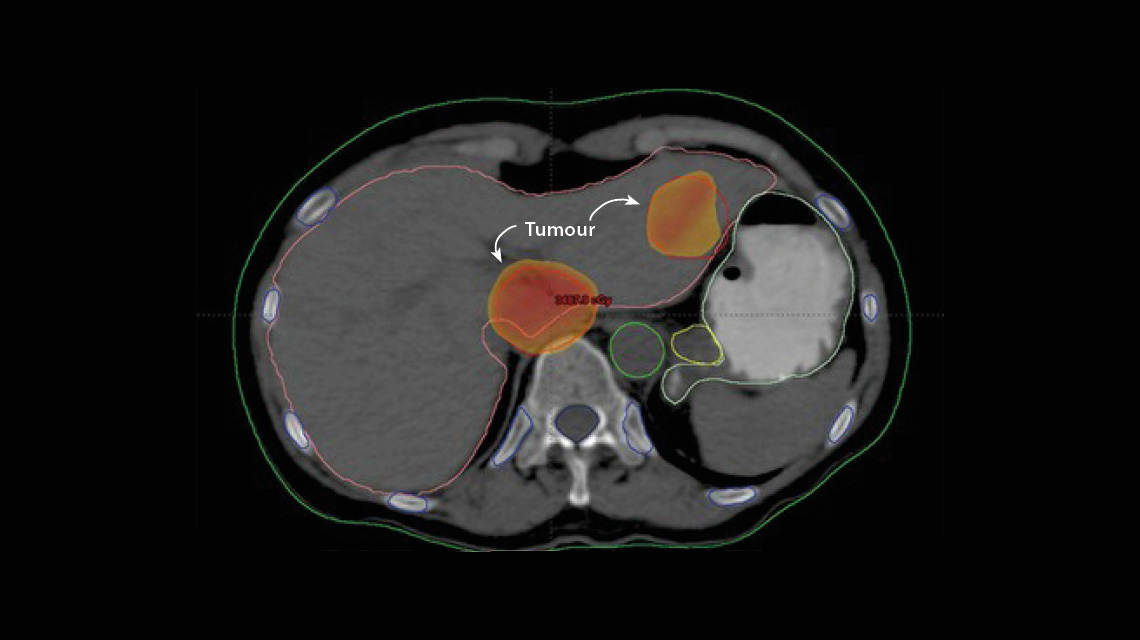

A case of liver cancer to be treated with an advanced radiotherapy method called stereotactic body radiation therapy.&nbsp;(Photo: National Cancer Institute, Egypt)

SBRT has taken control and precision to another level. What makes it unique is its use of 4-D images — height, width, depth, and, in some sites, motion — to plan and deliver very precise beams of radiation at a tumour from different angles. Each beam on its own has a lower radiation dose, which is safer and reduces the risk of side effects for normal tissue in its path. When the beams converge at the tumour, they expose the cancer cells to a greater combined dose of radiation. This generally means fewer sessions are needed to effectively treat a patient.

For liver cancers like HCC, SBRT has radically improved radiation treatment options, Shouman explained. Liver cancer is now the third most common cause of cancer deaths in the world. For years, this form of cancer could not be effectively treated using radiation; conventional radiotherapy cannot safely deliver radiation doses high enough to treat a liver tumour because of risks to the surrounding healthy liver tissue. With SBRT, even very small liver tumours can be treated with higher doses of radiation while preserving healthy tissue.